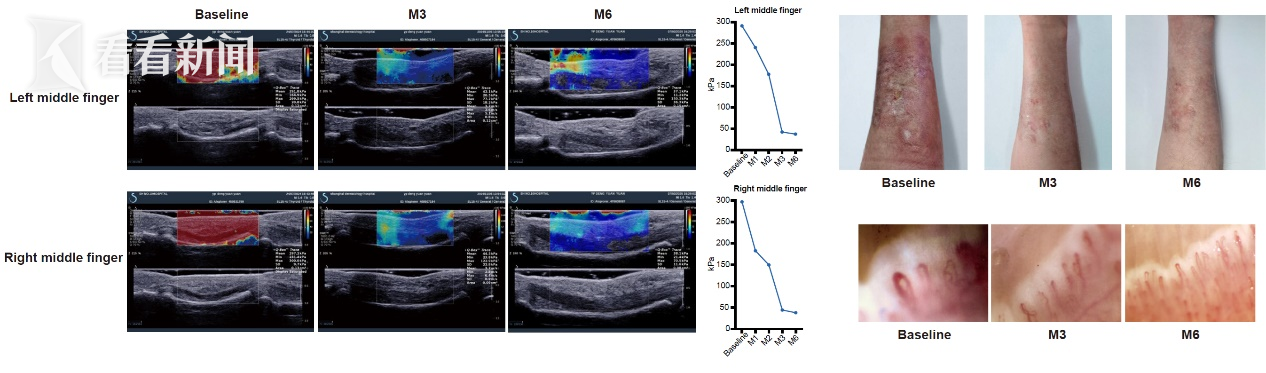

科研团队采用杭州启函基因生物有限公司开发的一种以诱导多能干细胞为基础的工程化CD19/BCMA双靶点嵌合抗原受体自然杀伤细胞(CAR-NK)产品(QN-139b),通过多基因编辑构建出免疫兼容性强、安全性高、功能稳定、具有批量生产潜力的新一代细胞治疗产品,系统解决了传统CAR-T治疗在自身免疫病中存在的诸多难题,并在难治性系统性硬皮病患者中实现了首例成功临床转化——治疗后患者皮肤硬化明显改善,组织纤维化显著逆转,肺功能和心脏功能等多项关键指标均取得了显著改善。

(图片:长征医院用CAR-NK疗法治疗一例40多岁的难治型硬皮病患者后,患者皮肤和血管情况明显好转)